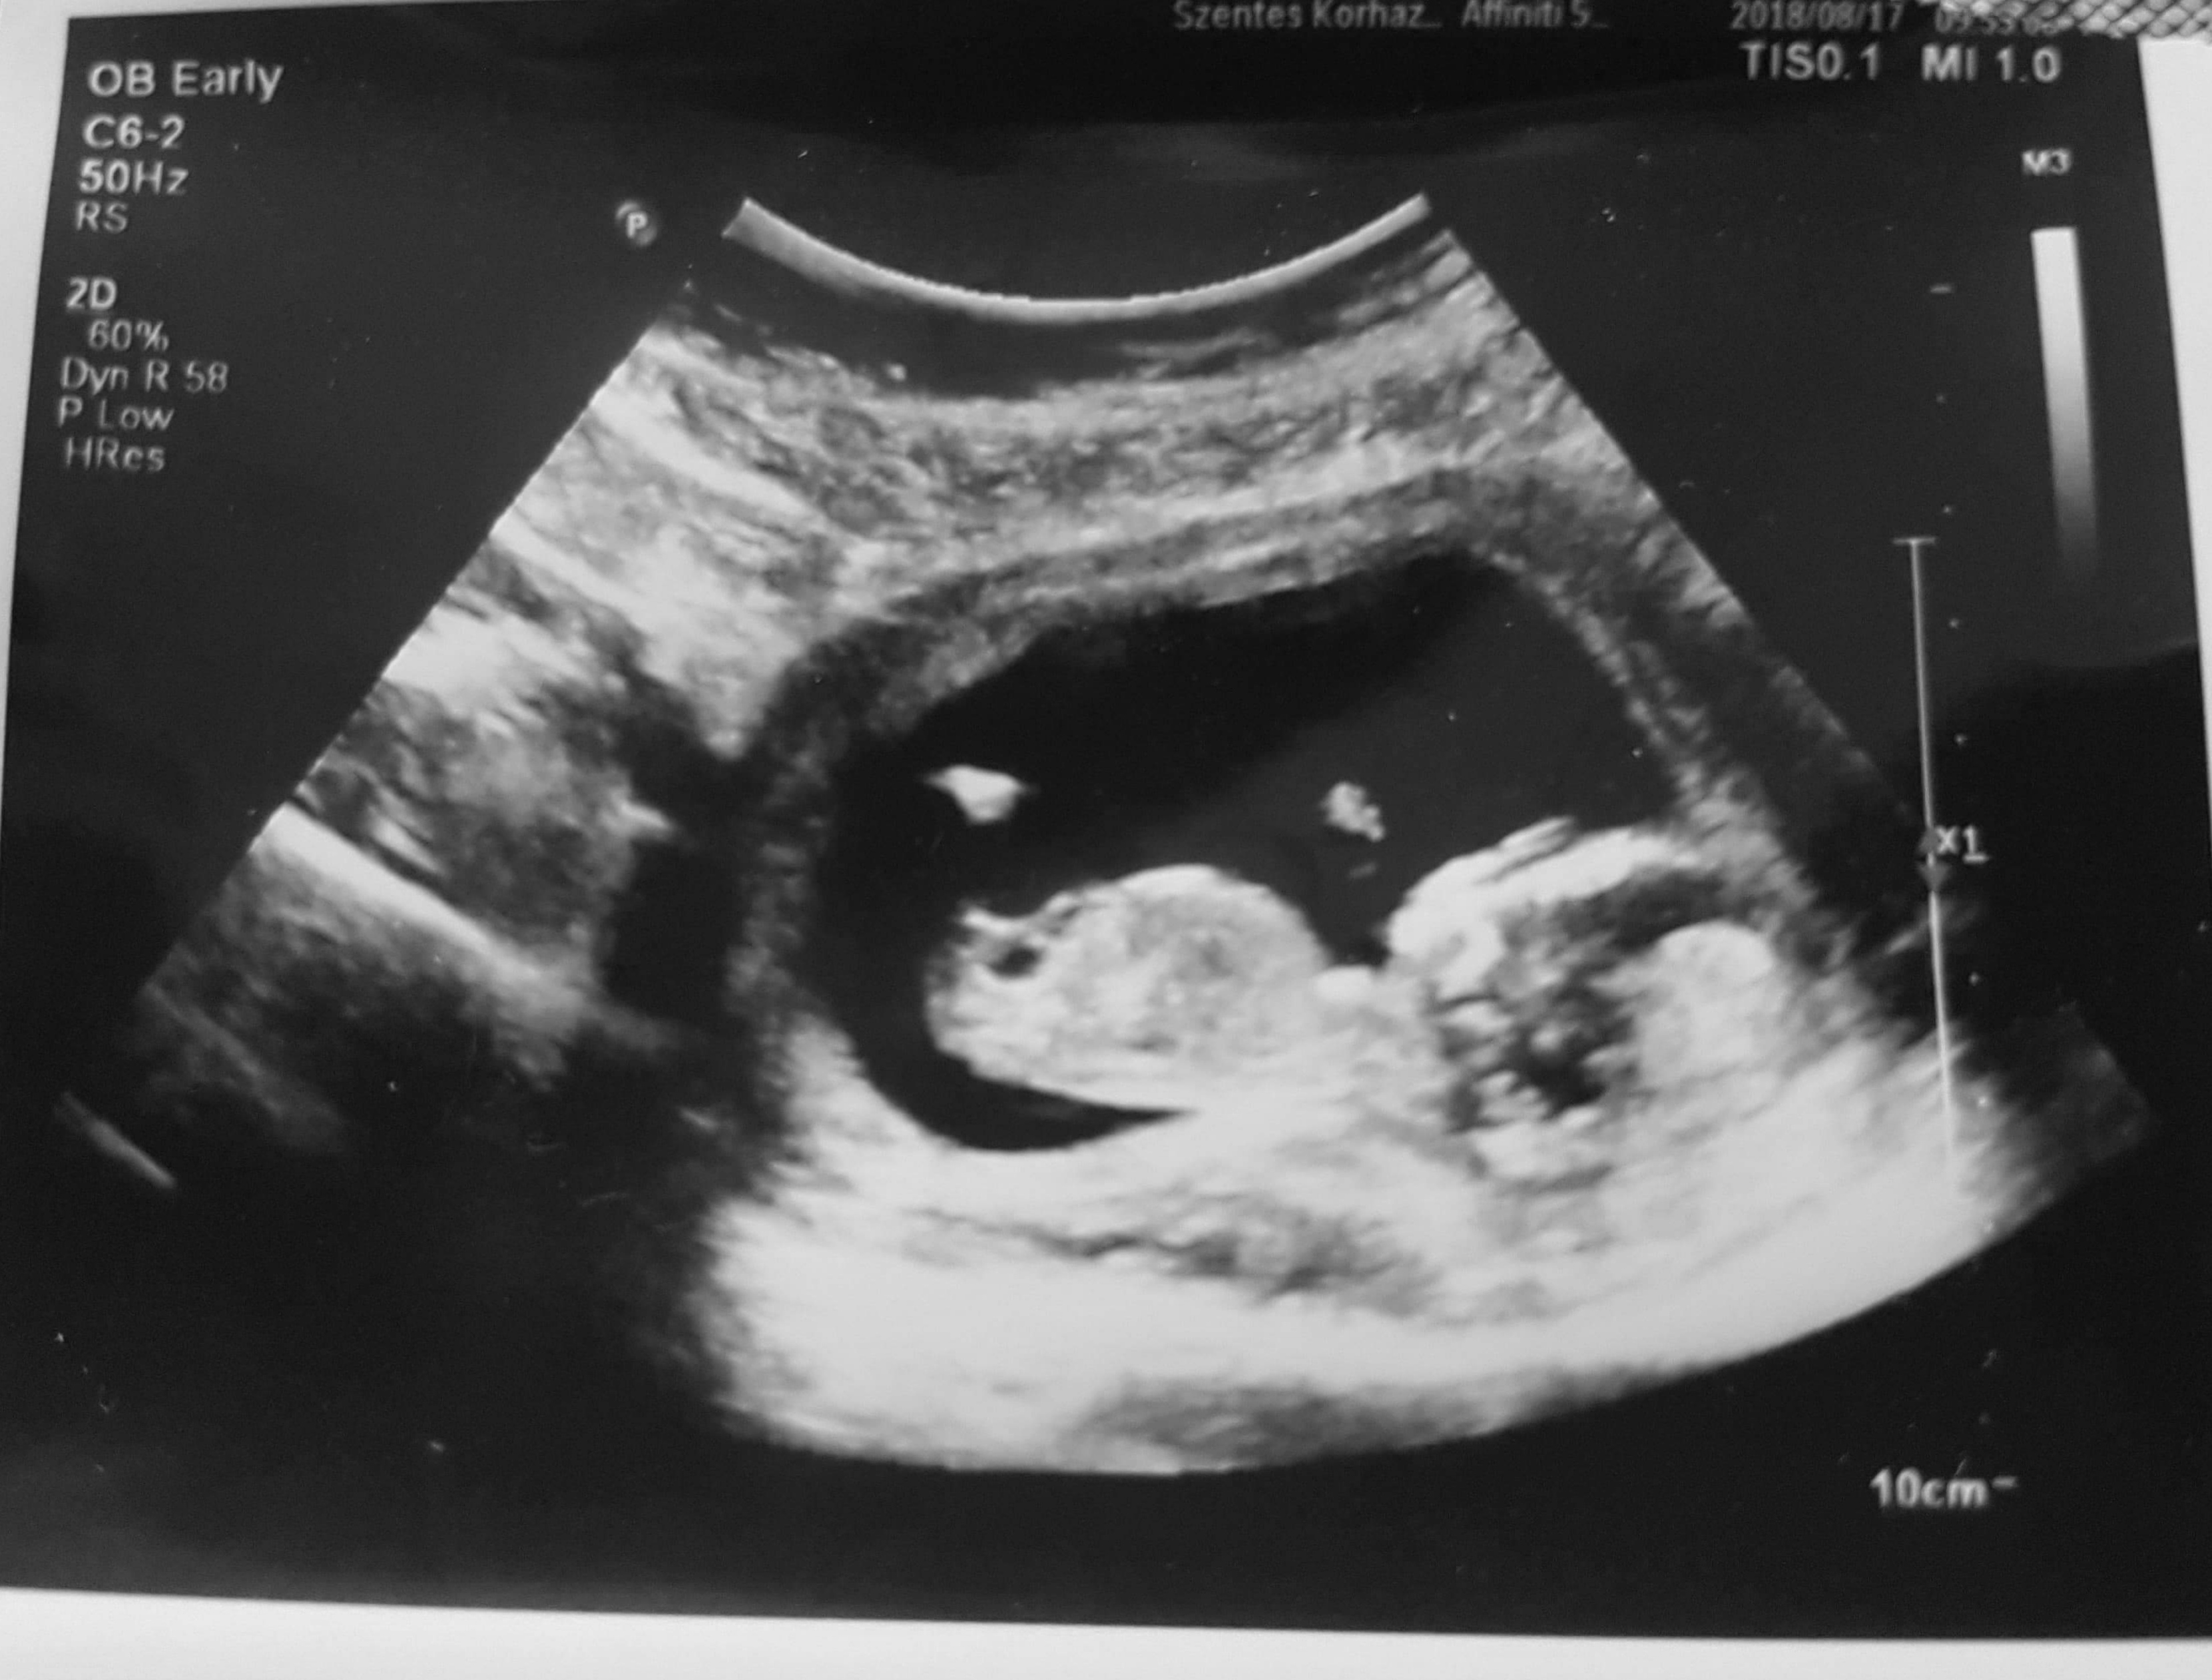

What gestation? Looks a bit early for nub guessing

Im in 14 weeks

Girl for 14 wks